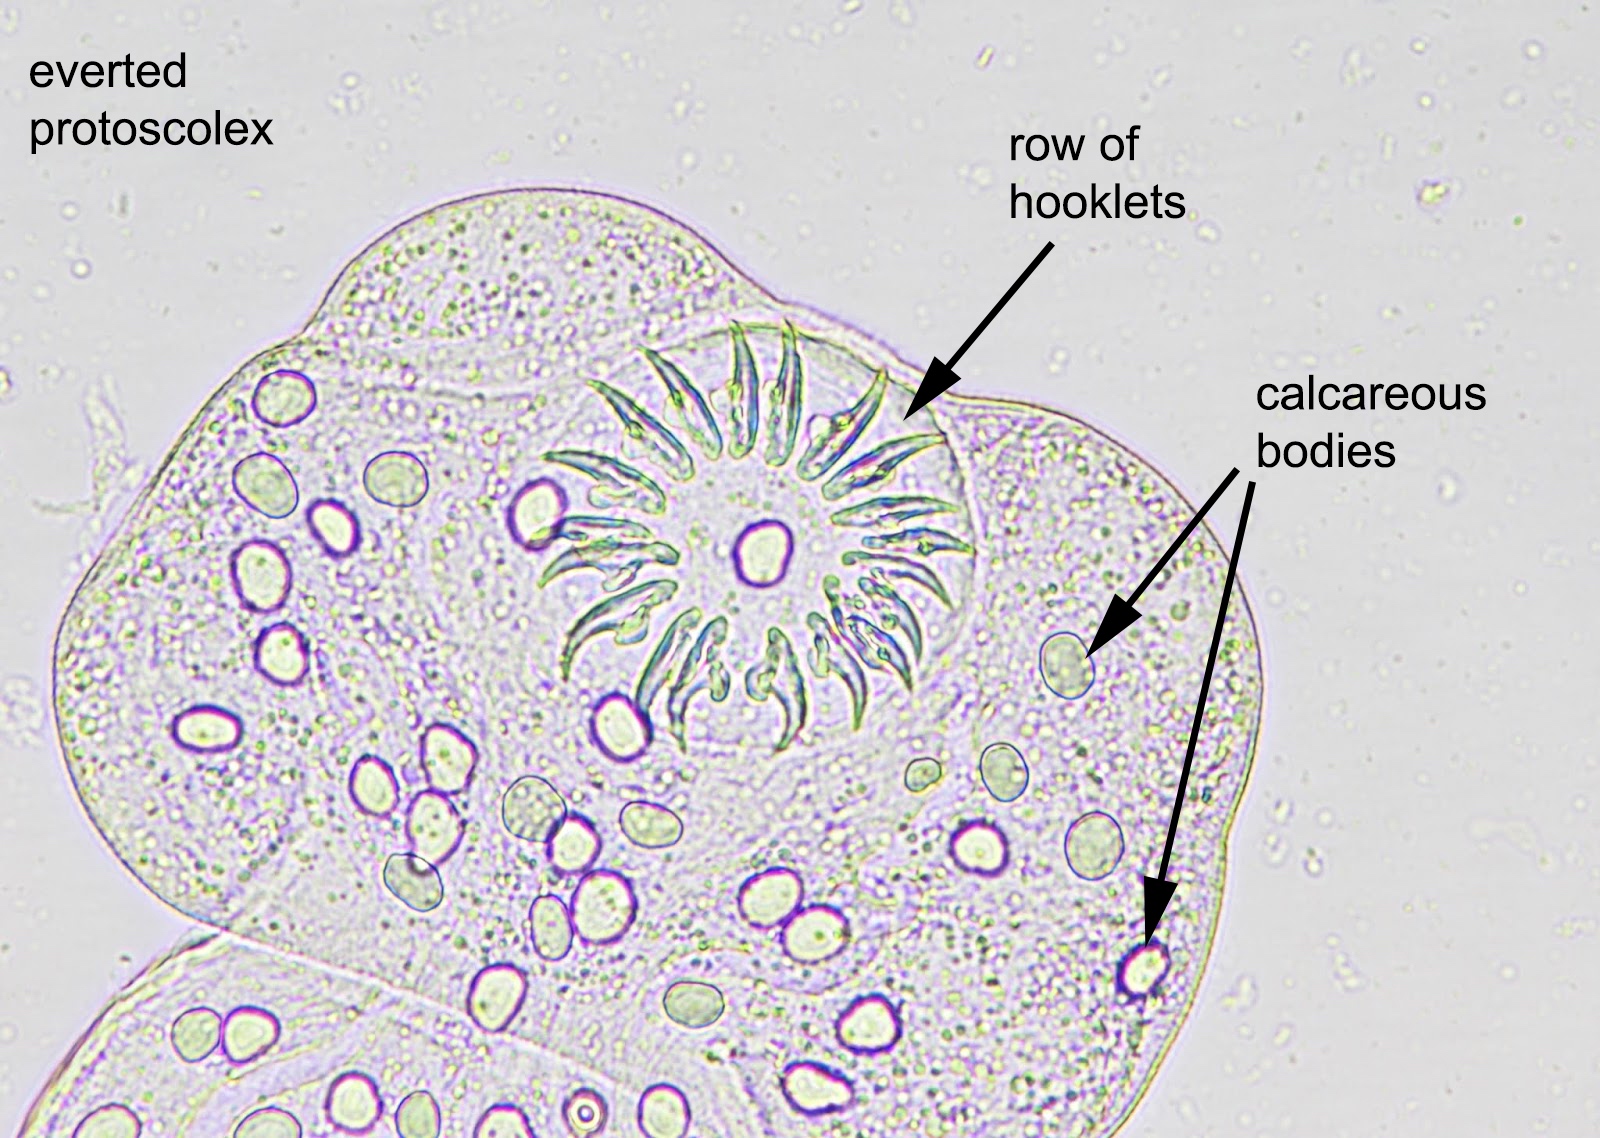

Microscopic (histologic) description

- E. granulosus

- Cyst wall has 3 structural components:

- Outer acellular laminated membrane (1 mm thick)

- Germinal membrane (a transparent nucleated lining)

- Protoscolices, attached to the membrane and budding from it

- Protoscolices are ovoid and contain hooklets (birefringent under polarized light) and a sucker

- Outer fibrotic layer with granulation tissue with increased eosinophils also exists

Microscopic (histologic) images

Positive stains

- Hooklets are acid fast positive on Ziehl-Neelsen stain; also stain with GMS (J Cytol Histol 2016;7:1000422)